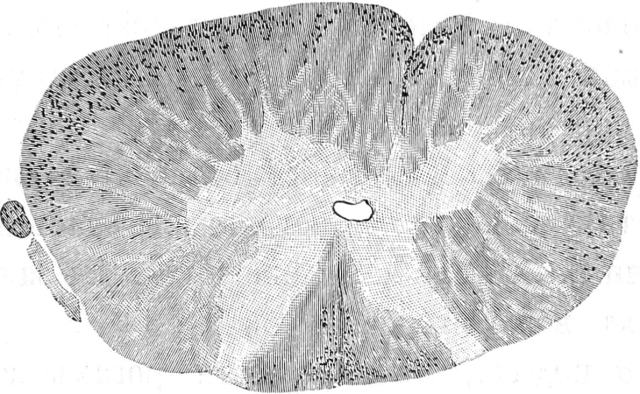

Названные авторы воспользовались съ одной стороны опытомъ Stenson’a а съ другой изслѣдованіями Conheim’a и Litten’a объ ишемическомъ некрозѣ, вполнѣ правильно предполагая, что замѣчаемый при перевязкѣ аорты параличъ заднихъ конечностей зависитъ отъ некроза сѣраго вещества спинного мозга и что при продолжительной перевязкѣ возможно сѣрое вещество совершенно разрушить; такимъ образомъ, пользуясь перевязкой брюшной аорты, они задались цѣлью вылущить,,herausschälen“ сѣрое вещество спинного мозга и, благодаря этому, узнать анатомическое отношеніе его къ окружающимъ частямъ. Для производства зажатія аорты они пользовались способомъ Du Bois-Raymond’a [22]). Зажимали брюшную аорту на 1 часъ. Въ большинствѣ случаевъ авторы наблюдали продолжительный двигательный и чувствительный параличъ задней половины животнаго. Въ спинномъ мозгу животныхъ, жившихъ послѣ перевязки брюшной аорты довольно продолжительное время, авторы нашли очень интересныя измѣненія: сѣрое вещество спинного мозга на всемъ протяженіи сильно съужено, такъ что оно приняло видъ двухъ изогнутыхъ узкихъ полосъ; міэлиновыя волокна сѣраго вещества уже не открываются по методу Weigert’a за исключеніемъ заднихъ роговъ, гдѣ еще остались нѣкоторыя изъ волоконъ; гангліозныя клѣтки исчезли совершенно, между тѣмъ какъ заднія корешки и спинныя гангліи совершенно нормальны.

Въ бѣломъ веществѣ авторы нашли также большія измѣненія: передніе и передне-боковые столбы, за исключеніемъ въ послѣднихъ двухъ узкихъ поясковъ, перерождены; одинъ изъ поясковъ, оставшійся неизмѣненнымъ, соотвѣтствуетъ по- мнѣнію обоихъ авторовъ, по всей вѣроятности, переднимъ пирамиднымъ пучкамъ, второй же соотвѣтствуетъ боковымъ мозжечковымъ пучкамъ человѣка. Такимъ образомъ, согласно изслѣдованію Ehrlich’a и Brieger’a все бѣлое вещество, исключая заднихъ и такъ называемыхъ длинныхъ пучковъ, перерождено.